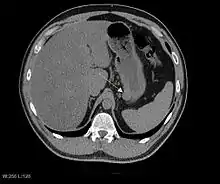

The purpose of radiologic imaging is to locate the lesion, evaluate for signs of invasion and detect metastasis. Features of GIST vary depending on tumor size and organ of origin. The diameter can range from a few millimeters to more than 30 cm. Larger tumors usually cause symptoms in contrast to those found incidentally which tend to be smaller and have better prognosis.[4][12] Large tumors tend to exhibit malignant behavior but small GISTs may also demonstrate clinically aggressive behavior.[13]

Preferred imaging modalities in the evaluation of GISTs are CT and MRI,[15]:20–21 and, in selected situations, endoscopic ultrasound. CT advantages include its ability to demonstrate evidence of nearby organ invasion, ascites, and metastases. The ability of MRI to produce images in multiple planes is helpful in determining the bowel as the organ of origin (which is difficult when the tumor is very large), facilitating diagnosis.

Large GISTs

As the tumor grows it may project outside the bowel (exophytic growth) and/or inside the bowel (intraluminal growth), but they most commonly grow exophytically such that the bulk of the tumor projects into the abdominal cavity. If the tumor outstrips its blood supply, it can necrose internally, creating a central fluid-filled cavity with bleeding and cavitations that can eventually ulcerate and communicate into the lumen of the bowel. In that case, barium swallow may show an air, air-fluid levels or oral contrast media accumulation within these areas.[13][16] Mucosal ulcerations may also be present. In contrast enhanced CT images, large GISTs appear as heterogeneous masses due to areas of living tumor cells surrounding bleeding, necrosis or cysts, which is radiographically seen as a peripheral enhancement pattern with a low attenuation center.[12] In MRI studies, the degree of necrosis and bleeding affects the signal intensity pattern. Areas of bleeding within the tumor will vary its signal intensity depending on how long ago the bleeding occurred. The solid portions of the tumor are typically low signal intensity on T1-weighted images, are high signal intensity on T2-weighted images and enhance after administration of gadolinium. Signal-intensity voids are present if there is gas within areas of necrotic tumor.[14][17][18]

Malignancy is characterized by local invasion and metastases, usually to the liver, omentum and peritoneum. However, cases of metastases to bone, pleura, lungs and retroperitoneum have been seen. In distinction to gastric adenocarcinoma or gastric/small bowel lymphoma, malignant lymphadenopathy (swollen lymph nodes) is uncommon (<10%) and thus imaging usually shows absence of lymph node enlargement.[12] If metastases are not present, other radiologic features suggesting malignancy include: size (>5 cm), heterogeneous enhancement after contrast administration and ulcerations.[4][12][19] Also, overtly malignant behavior (in distinction to malignant potential of lesser degree) is less commonly seen in gastric tumors, with a ratio of behaviorally benign to overtly malignant of 3-5:1.[4] Even if radiographic malignant features are present, these findings may also represent other tumors and definitive diagnosis must be made immunochemically.